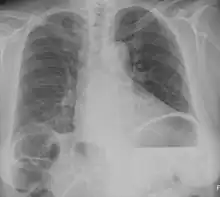

Chest X-ray of the same patient as the picture above. A small crescent of air can be seen under the right part of the diaphragm, caused by Chilaiditi's sign. However, it could easily be mistaken for free intra-abdominal air (pneumoperitoneum) which could mistakenly be attributed to bowel perforation.

Normally this causes no symptoms, and this is called Chilaiditi's sign. The sign can be permanently present, or sporadically. This anatomical variant is sometimes mistaken for the more serious condition of having air under the diaphragm (pneumoperitoneum) which is usually an indication of bowel perforation, possibly leading to surgical interventions.